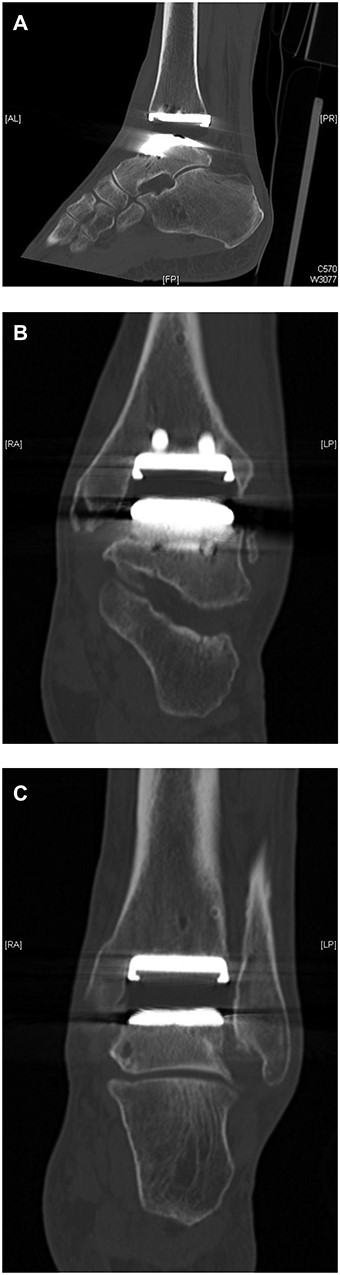

CT demonstration of the poly liner sitting slightly outside of its groove ‘the gap sign’ (A) Lateral view showing ct gap sign (B). AP view showing gap (C). AP view showing poly seating.

All inflammatory markers were within normal limits. Upon suspicion that the talar component might be irritating the tibialis posterior tendon, he underwent an ultrasound which was normal. His computed tomography (CT) was reported as normal by the radiologist. Symptoms suggested possible impingement of a slightly oversized talar component on medial malleolus. On close scrutiny, it was apparent that the CT postoperatively showed the poly to be seated anteriorly with a failure to engage posteriorly, leaving a void in the socket. We describe this as a ‘CT GAP sign’ (Fig. 1A–C), and he was offered a revision ankle replacement.